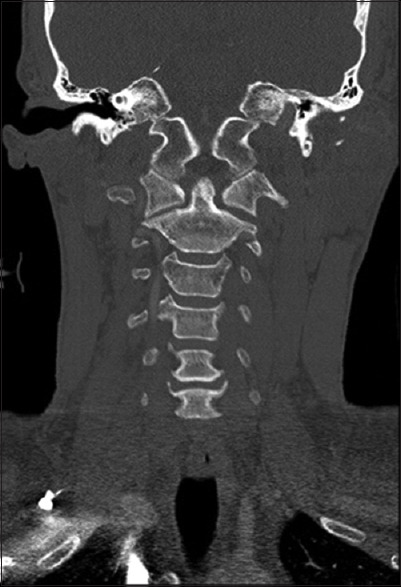

Methods: After receiving Institutional Review Board approval, all magnetic resonance imaging (MRI) and computed tomography (CT) radiology reads from January 1, 2006, to August 1, 2021, at our Level I Trauma Center were queried for the following terms: edema, disruption, avulsion, tear, distraction, or subluxation and transverse ligament, AAJ, or C1-C2 joint, resulting in 2779 patients. Inclusion criteria consisted of age greater than 18 years old, history of recent traumatic injury, and radiographic evidence of unilateral AAJ distraction on CT, defined by a unilateral lateral mass index (LMI) >2.6 mm. MRI scans were classified based on the extent of soft-tissue injury. Demographic data and clinical outcomes were obtained by chart review and summarized using descriptive statistics.

Results: Five patients comprised this study: 3 males and 2 females with an average age of 51 years. Four patients were injured by motor vehicle accident and 1 due to fall from standing height. Three patients had concomitant orthopedic extremity fractures requiring operative fixation. The average LMI of the involved joint was 4.2 mm versus 2.0 in the contralateral joint. On MRI, 3 patients exhibited bilateral AAJ effusions. No patients demonstrated complete injury of associated ligaments. All patients were treated conservatively with a rigid cervical collar. No patients demonstrated late instability at an average radiographic follow-up of 876 days.